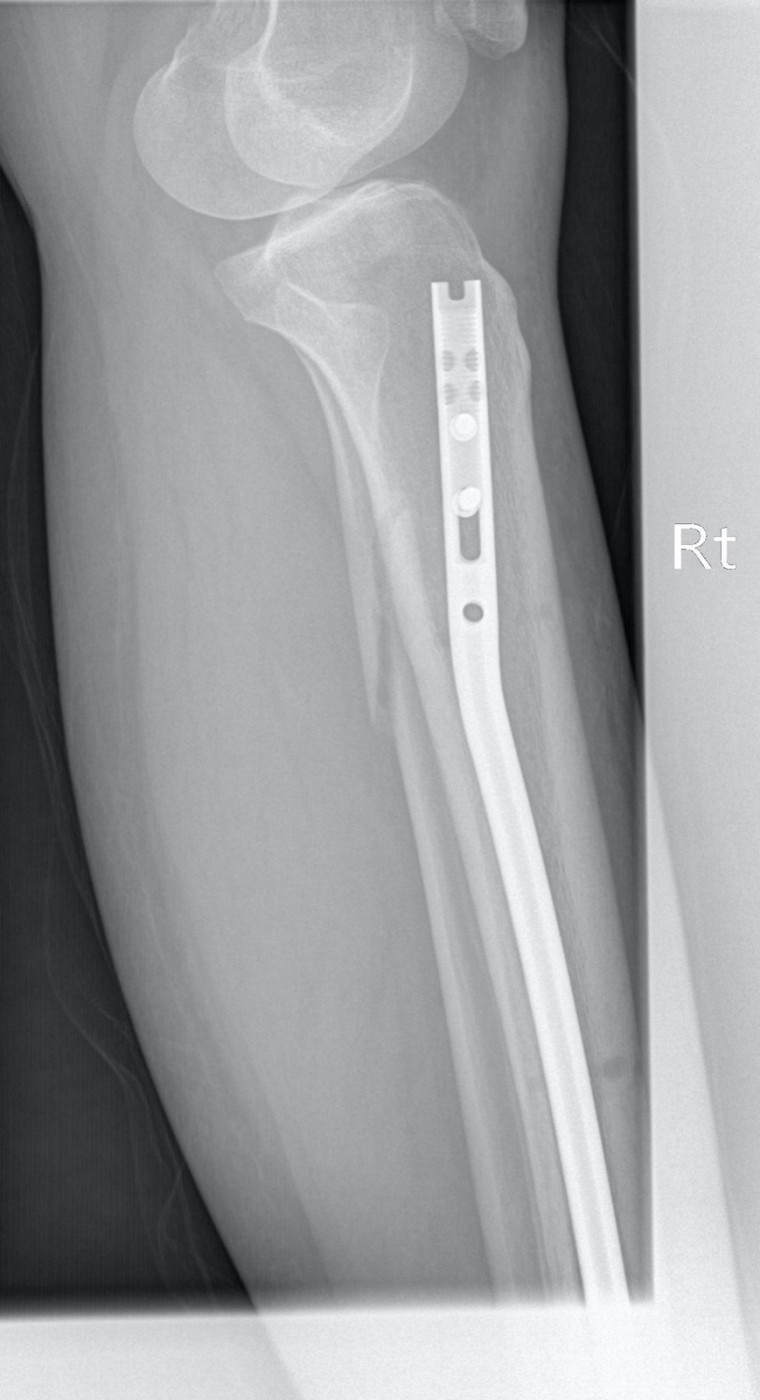

Перелом внутренней лодыжки у ребенка